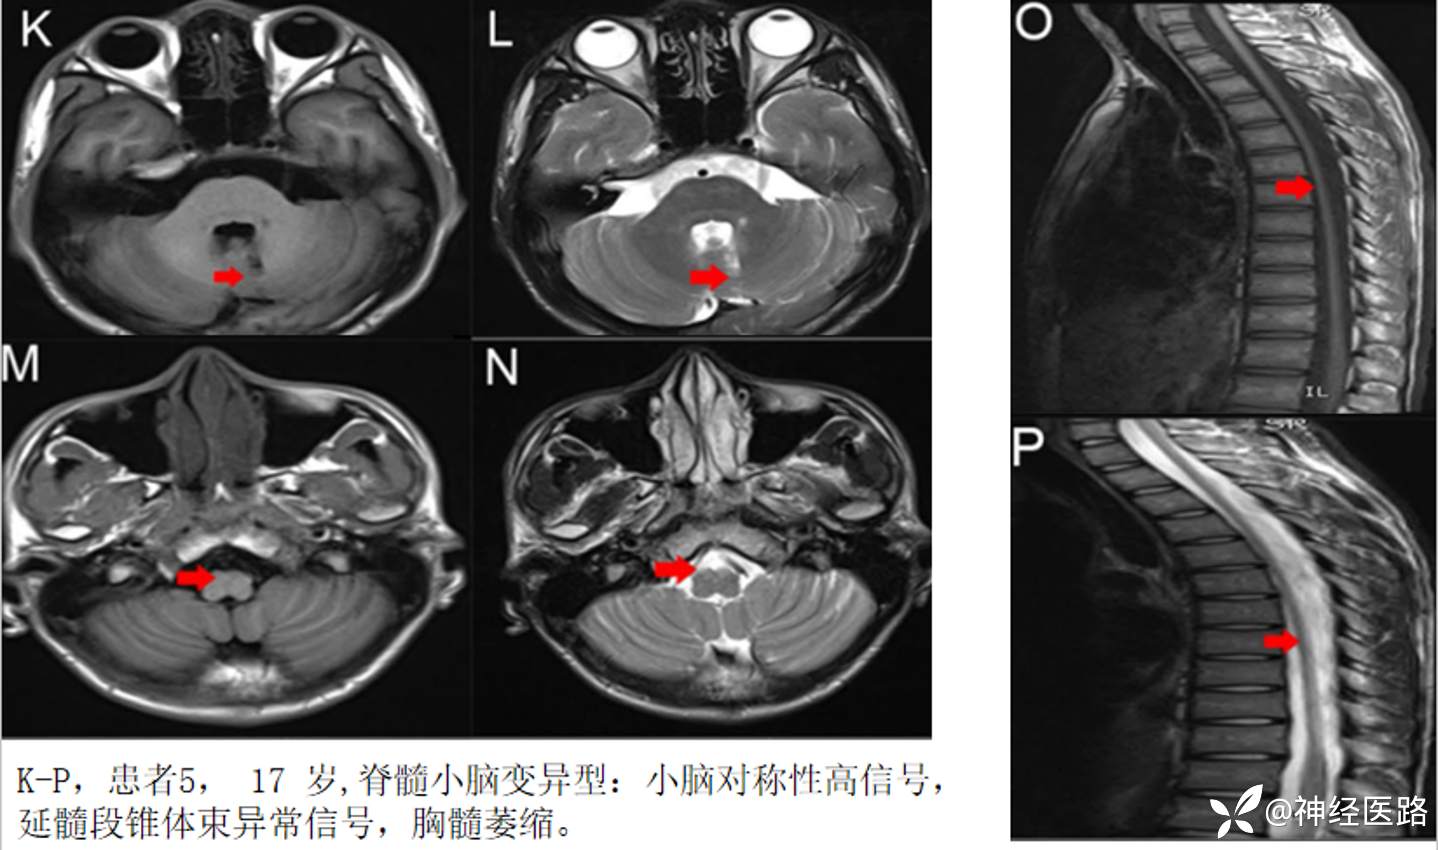

AMN中罕见表型可以脑干和(或)小脑表现为主,命名有多种,包括以脊髓小脑变性为表现的AMN、橄榄桥脑小脑型、小脑型、共济失调型、脊髓小脑型等。

脊髓小脑变异型肾上腺脊髓神经病小脑病变多表现实质内异常信号,而非萎缩。